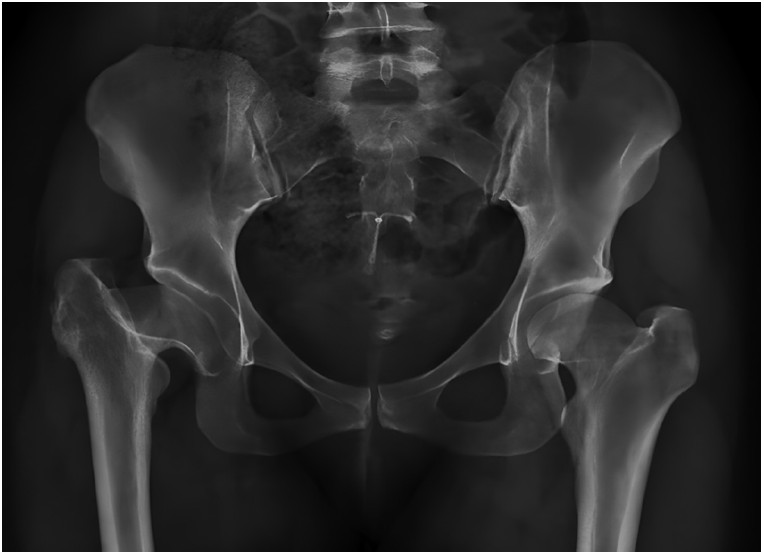

Después de la aprobación del protocolo de estudio por el Comité de Ética de Protocolos de Investigación del hospital y la firma del consentimiento informado, se incluyeron pacientes para cirugía primaria de cadera con antecedentes de DDC tipo I y II de la clasificación de Crowe y secuelas de Perthes de forma prospectiva, entre Enero de 2019 y Marzo de 2020, con un seguimiento mínimo de 24 meses. Se excluyeron pacientes con infección previa, implantes remanentes y fracturas.

Evaluación radiográfica

La anteversión acetabular tuvo un promedio de 10o (IQR 0o-15o), no observándose componentes acetabulares retroversos. El ángulo de inclinación tuvo una mediana de 43o (rango intercuartílico [RIC]: 38o a 51o). En dos (9.9%) pacientes se detectaron líneas radiolúcidas sin progresión o significancia clínica; el resto de los sujetos presentaron cinco de los signos radiográficos de Moore para osteointegración del cotilo. En 20 pacientes (90.1% de la serie), la medición postoperatoria de la longitud de los miembros no encontró discrepancia entre el operado y el contralateral, en un caso se presentó una hipermetría menor a 0.5 cm y una hipermetría entre 0.5 a 1 cm. En ningún caso hubo disconformidad con el resultado funcional. Se detectó la aparición de calcificaciones heterotópicas de tipo 1 (clasificación de Brooker) en dos casos, sin ninguna relevancia clínica.